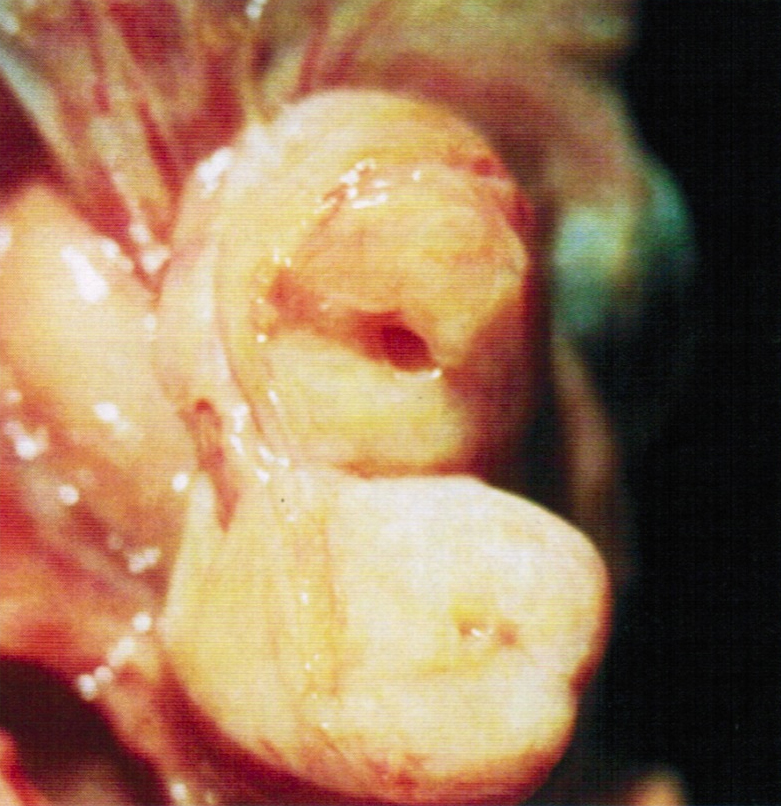

Gross description

- Firm, nodular swellings of the fallopian tube, ranging in size up to 2 cm in greatest dimension (Br J Radiol 2021;94:20201386)

- May be unilateral or bilateral

- Smooth, intact serosal covering

- Cross section of the nodules reveal gray, yellow or brown tissue punctuated by small cysts that surround the original tubal lumen (StatPearls: Salpingitis Isthmica Nodosa [Accessed 22 June 2023])

- Nodosity of the isthmus may give the uterus a horned appearance

Gross images